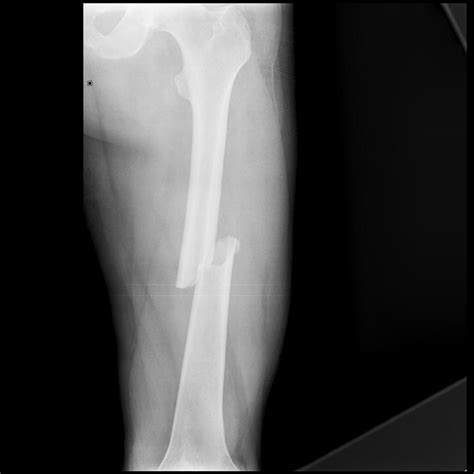

Understanding the intricacies of an Xray of broken bones is crucial for both medical professionals and patients. This diagnostic tool plays a pivotal role in identifying fractures, assessing their severity, and planning appropriate treatment. Whether you are a healthcare provider or someone who has experienced a bone injury, grasping the fundamentals of X-ray imaging can provide valuable insights into the healing process and overall recovery.

When a bone is fractured, the continuity of the bone is disrupted, creating visible gaps or misalignments on the X-ray image. These disruptions can range from simple cracks to complex fractures involving multiple bone fragments. The Xray of broken bones helps medical professionals determine the type and extent of the fracture, which is essential for developing an effective treatment plan.

Interpreting an Xray of broken bones requires a trained eye and a thorough understanding of bone anatomy. Radiologists look for specific signs of fractures, including:

• Discontinuity of the Bone: Visible gaps or breaks in the bone structure.

• Misalignment: Bones that are not properly aligned, indicating a fracture.

• Overlapping Fragments: Bone fragments that overlap, suggesting a comminuted fracture.

• Soft Tissue Swelling: Swelling around the fracture site, which can indicate the severity of the injury.